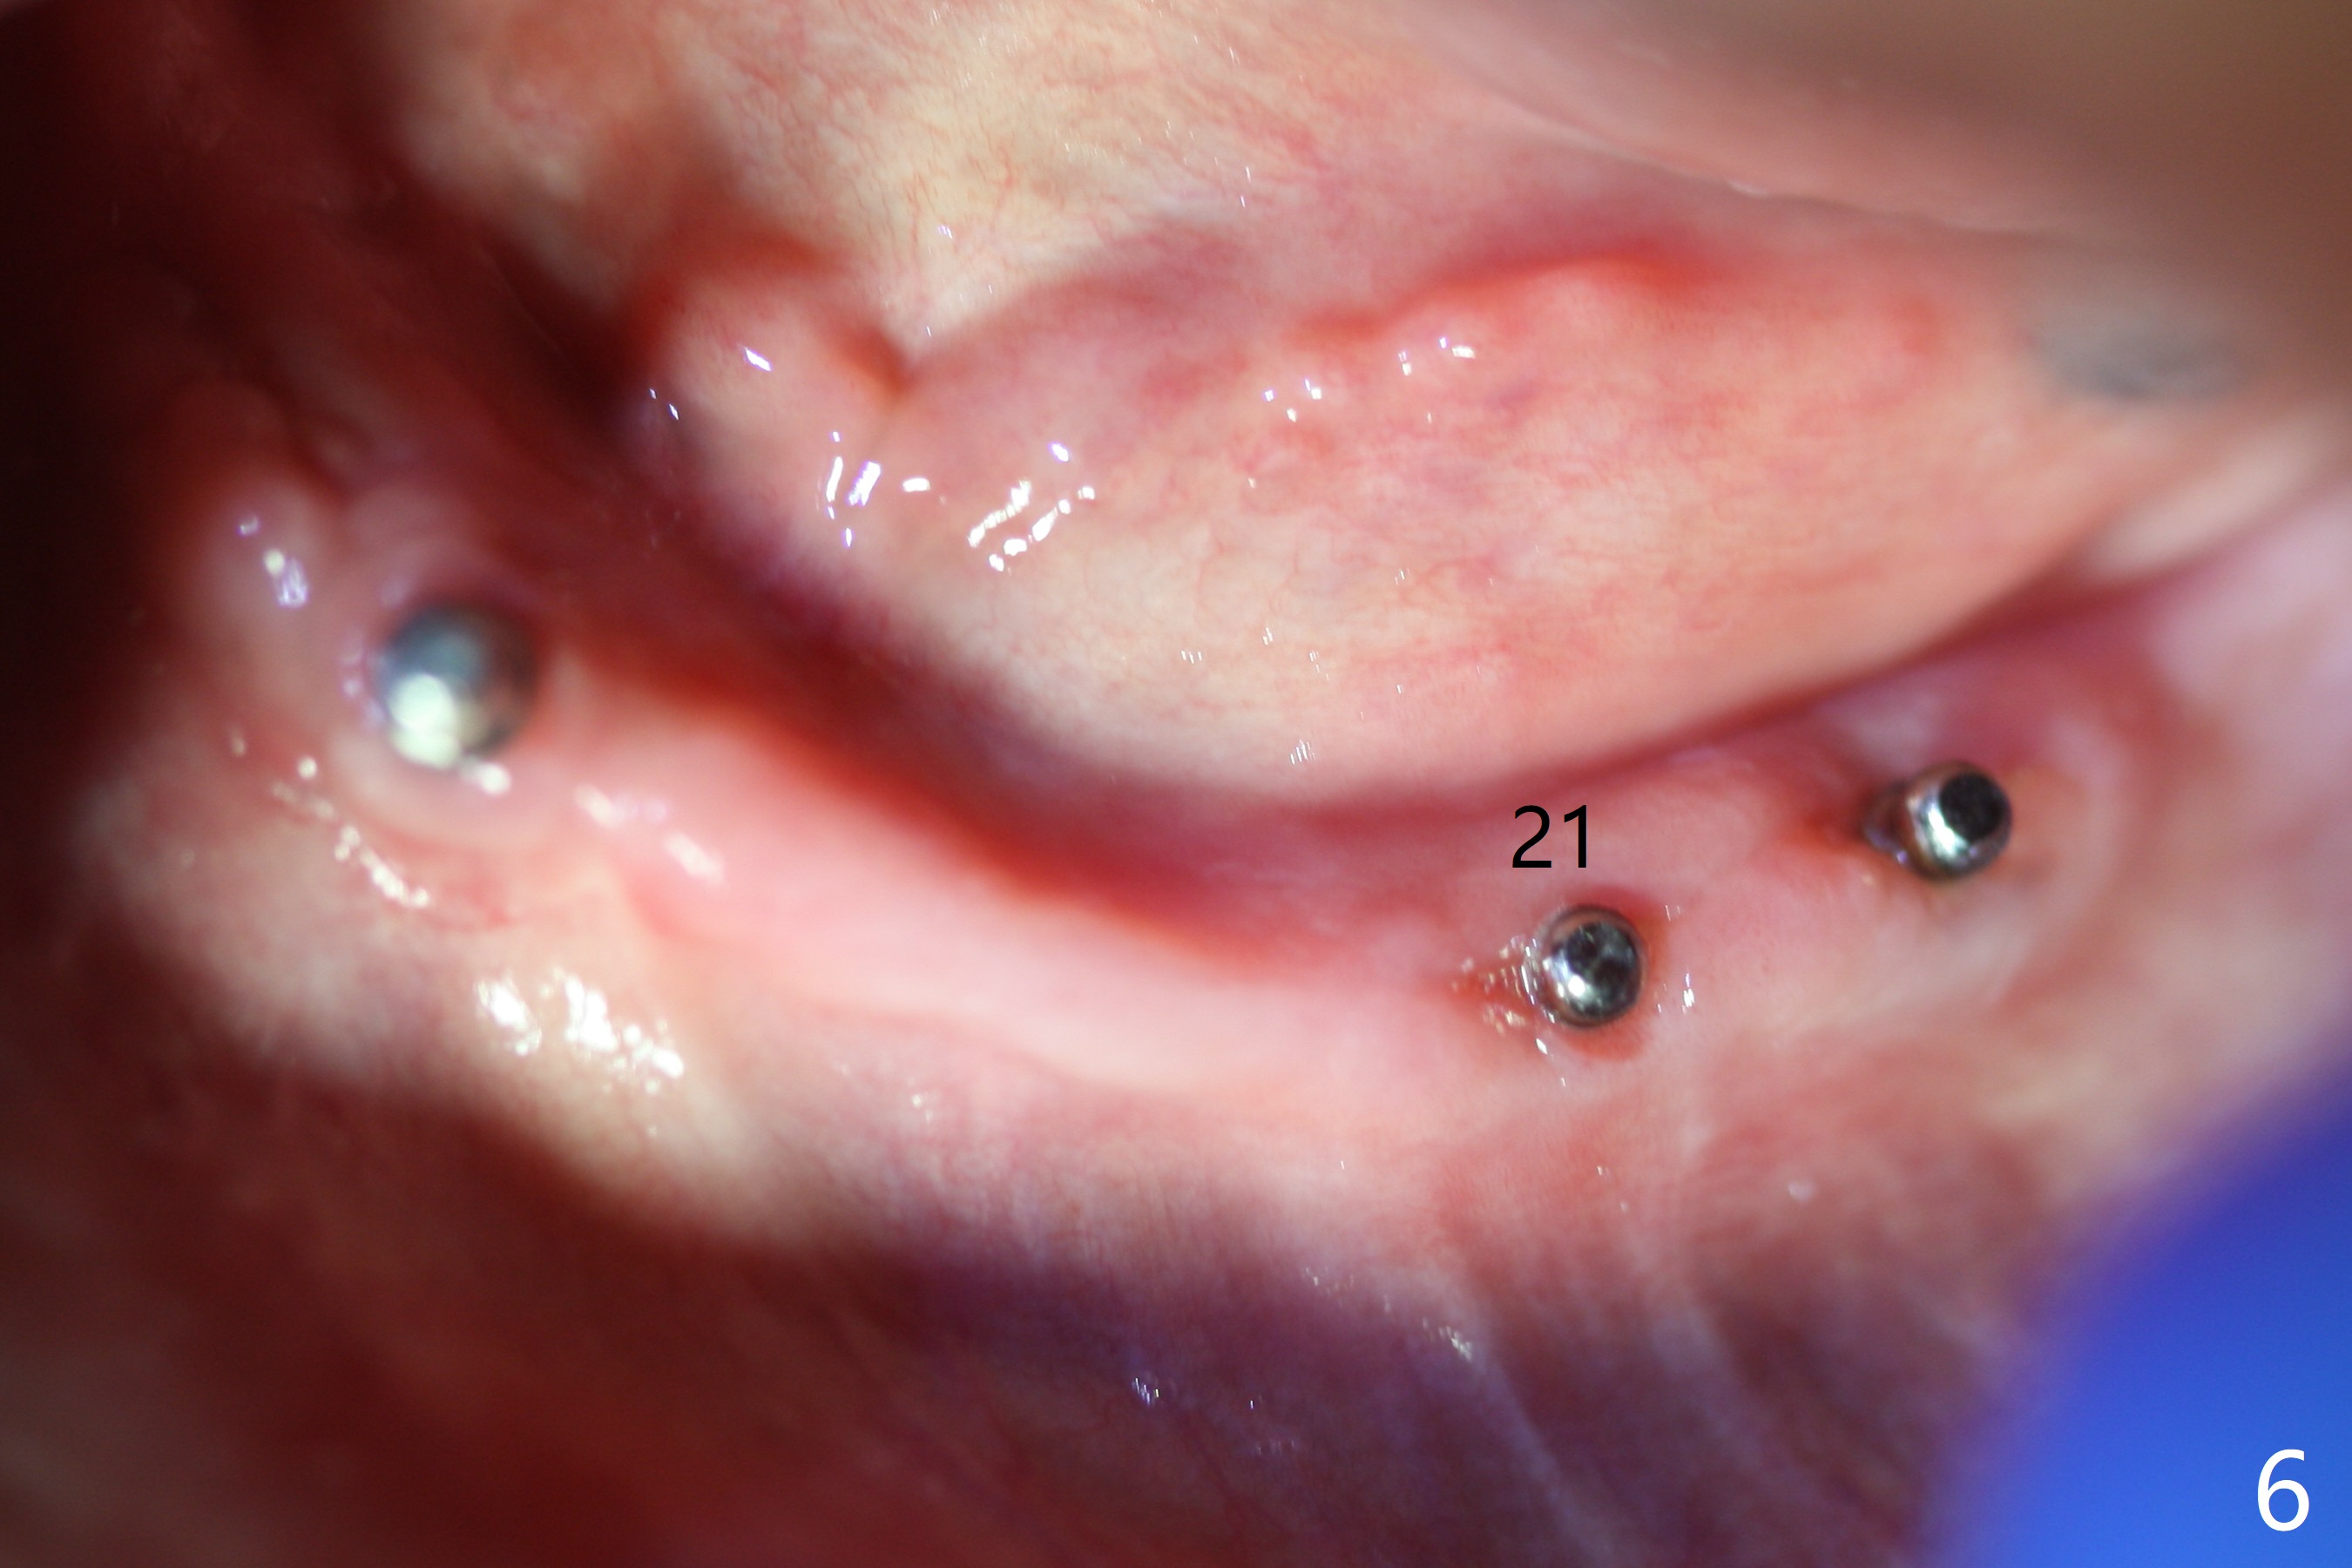

When the patient returns 4 months post #26 implant 2nd placement, the fractured crowns at #20 and 21 are loose. The roots are not difficult to remove. Since the bone height is limited (Fig.1,2), immediate implants are 3.8x8 and 3.8x10 mm, respectively with insertion torque >30 Ncm. Ball abutments (3.9x2 mm) are placed at #20 and 21; the existing lower RPD is soft relined using #26 1-piecee implant as an abutment. The retention of the RPD improves. Another implant will be placed in the lower right quadrant. One month 10 days postop, the ball abutment at #21 seems to be low (Fig.6). It is removed after laser gingivectomy and replaced with a ball abutment with 4 mm cuff. When the patient closes without RPDs, the 1-piece implant at #26 is barely buccal to the upper ridge (Fig.7). It appears that crowns have to be fabricated at #20,21,26 and 27 prior to refabrication of the lower RPD.